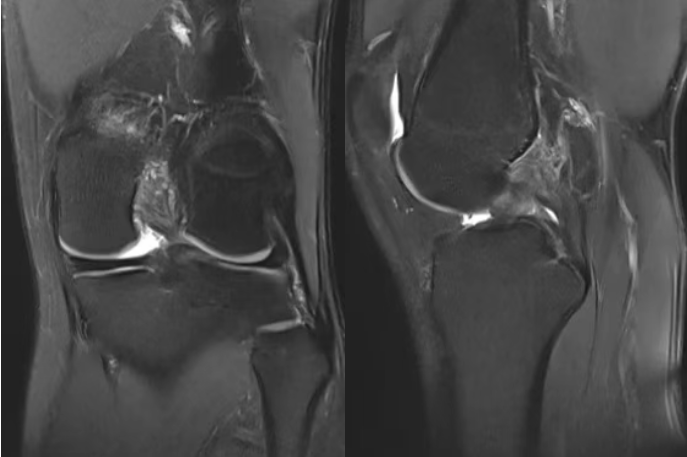

后交叉韧带位于膝关节最深部,起自股骨内髁外侧面前部,向后下方延伸,止于胫骨平台后方斜坡。该韧带比前交叉韧带更粗大和强壮。

后交叉韧带的主要功能是抵抗胫骨后移,作为防止小腿骨相对于大腿骨向后错位的最主要结构,在上下坡、下楼梯和减速奔跑时起着关键的稳定作用。